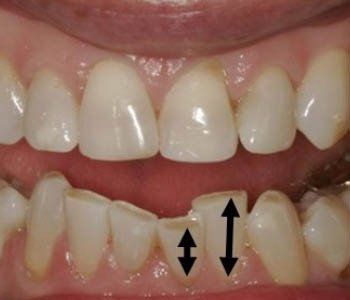

Diastema or Spacing

There is spaces or gaps between the teeth.